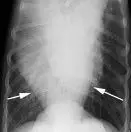

With increased opacity, many diseases will present with a mixed pulmonary pattern, so the dominant pattern should be identified to formulate an appropriate differential list (Figure 5). More important, the anatomic distribution will drive the prioritization process for differentials. For example, cranioventral typically equates with infectious disease (bacterial pneumonia), whereas caudodorsal typically equates with edema (cardiogenic or noncardiogenic).

Lateral radiographs from various dogs with increased lung opacity; ventral alveolar pulmonary pattern (A), generalized bronchial pulmonary pattern (B), vascular pulmonary pattern in a dog with a left-to-right shunting patent ductus arteriosus (C), structured interstitial pulmonary pattern in a dog with pulmonary nodules secondary to renal carcinoma metastatic disease (D), and an unstructured interstitial pulmonary pattern (E)